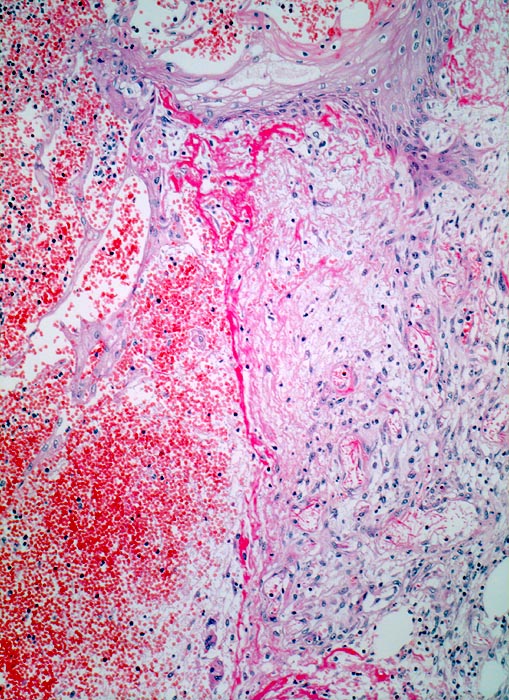

• Schlitzförmiger, bis in die Subkutis reichender Hautdefekt.

• Neugebildete Epidermis bedeckt im oberen intradermalen Anteil des Wundspaltes teilweise den Gewebsdefekt.

• Daran angrenzender Wundspalt im Bereich des subkutanen Fettgewebes mit Fibrinauflagerungen und ödematösem zellarmem Granulationsgewebe.

• An der Basis des Präparates Auseinanderklaffen des Wundspalts wegen grösserem Blutkoagel (verursacht Wundheilungsstörung).